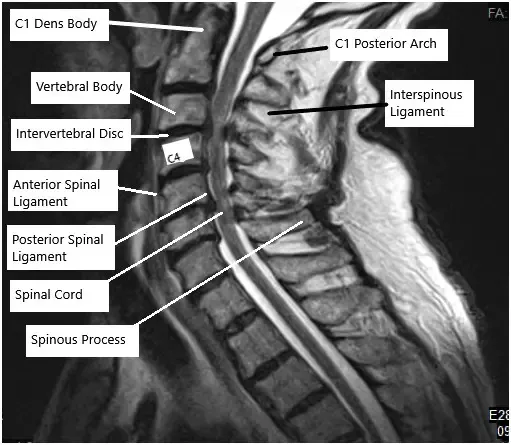

Resonancia magnética de la columna cervical

El diagnóstico por imagen avanzado, como la resonancia magnética, ayuda a confirmar el diagnóstico y a planificar el abordaje quirúrgico identificando la patología específica.